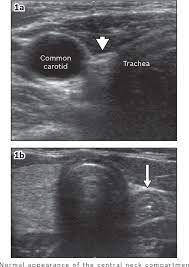

Spread of thyroid cancer to the lymph nodes in the neck is common and increases the risk of cancer recurrence. I had an ultrasound done in 2012 but the report for this scan never reached my previous doctor's practice and so nothing was. Ultrasound uses sound waves to create images of the body on a computer monitor. 8.4, 8.5, 8.6, 8.7, and 8.8). The first lymph node cancer cells spread to is known as the sentinel node.

An ultrasound of the thyroid produces pictures of the thyroid gland and the adjacent structures in the neck. The scan is painless and only takes a few minutes. It can detect abnormal tissues, growths, and cysts and give a suspicion of cancer based on how those images look. Confirming that a lump in the neck is developing from the thyroid or connected tissue. Doctors and pathologists do not use internal ultrasound scan frequently to detect lymphoma. Ultrasound guidance is used to perform thyroid biopsies and improves the diagnostic accuracy of fine needle biopsy. The first lymph node cancer cells spread to is known as the sentinel node. Ultrasounds can't show lung cancer or bone cancer. Some of the indications for thyroid or neck ultrasound are thyroid nodules, goiter, thyroid cancer and other neck masses. For neck or thyroid mass see ent. To see whether the cancer has spread, some or all of the lymph nodes are removed and checked for cancerous cells. Fna might also be used in patients whose cancer has been treated by surgery and/or radiation therapy , to help find out if a neck mass in the treated area is scar tissue or if it's a return (recurrence) of the cancer. The lymph nodes in the neck are often the first place cancer cells spread to outside the primary site.

Figure 1 From Post Thyroidectomy Neck Ultrasonography In Patients With Thyroid Cancer And A Review Of The Literature Semantic Scholar from d3i71xaburhd42.cloudfront.net I have ocd and my obsession of 30 years is that i have a tumor on in my throat or neck. Additionally, how do they test for thyroid cancer? An ultrasound scan of the neck uses sound waves to build up a picture of your neck and lymph nodes. Ultrasounds can't show lung cancer or bone cancer. The diagnosis of papillary thyroid cancer is made with an ultrasound guided small sampling of cells from the thyroid gland or neck lymph nodes (or both in some instances). Our doctors also use ultrasound to check lymph nodes in the neck, where some forms of thyroid cancer can spread. For most types of cancer, a biopsy is the only sure way for the doctor to know if an area of the body has cancer. We prospectively studied 19 patients referred to the institut gustave.